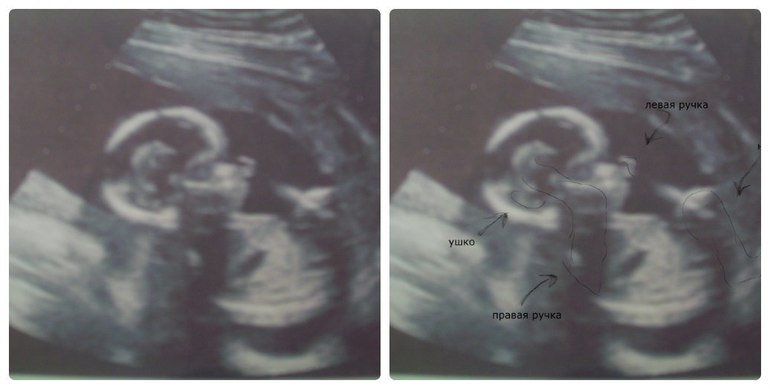

здесь 16 нед и 2 дня. по месячным. но он у меня опережает на недельку. Получается по мес 16+2, по плоду — 17+4

Так прикольно на них смотреть на узи))) Такие крохотульки))) Симпотяжечка)))

ага)) спасибо)) мне кажется таким красиивеньким

.хотя еще ничего толком-то не разглядишь))